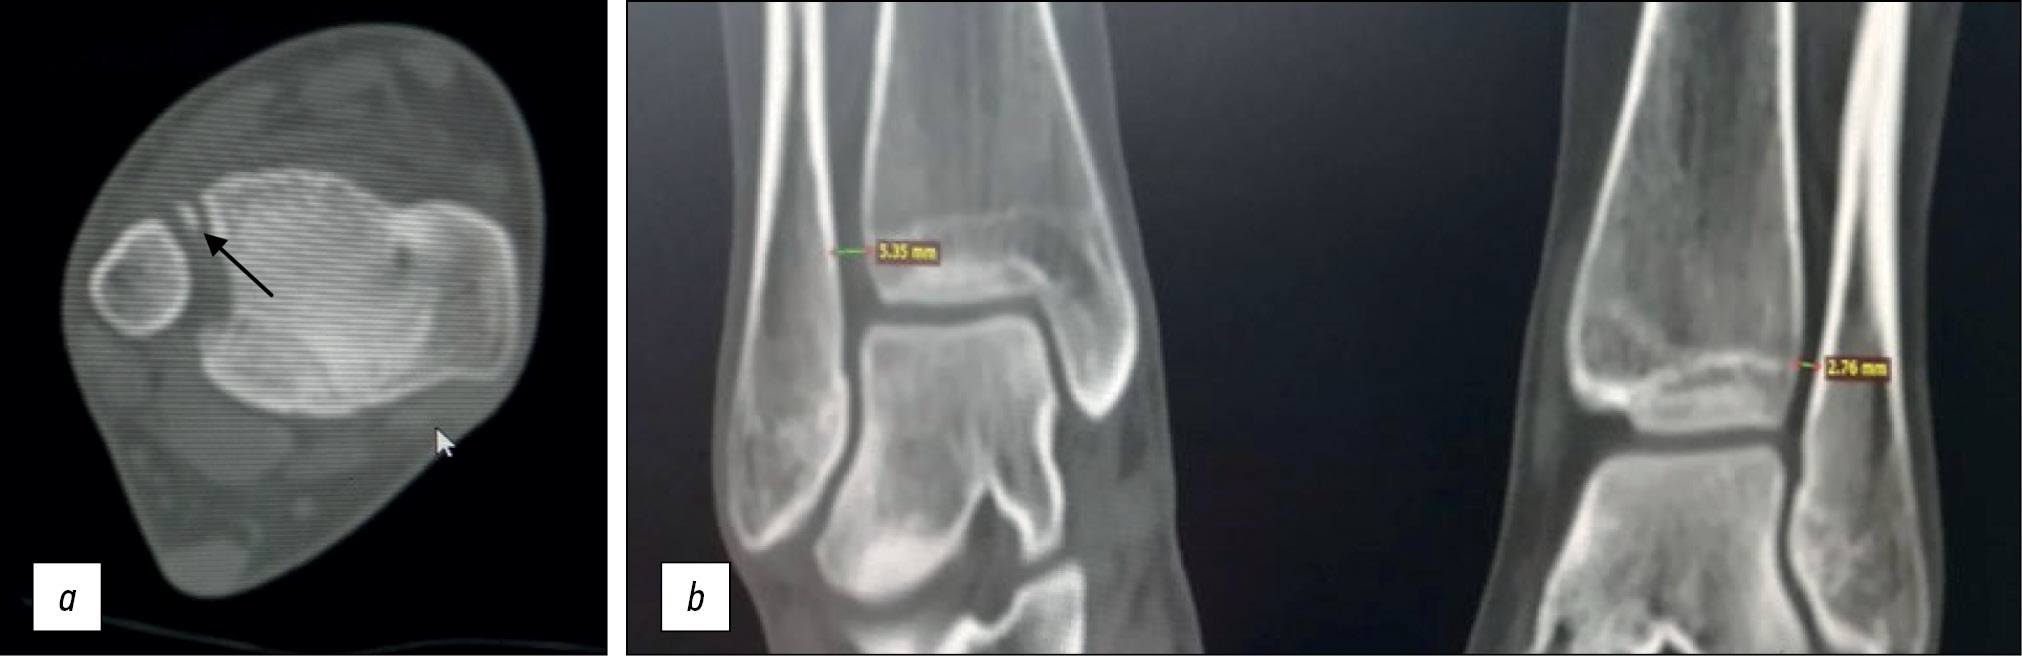

Для уточнения величины и степени смещения свободного костного фрагмента выполнена компьютерная томография (рис. 4). Свободный костный фрагмент оказался бугорком переднего края большеберцовой кости, в связи с его небольшими размерами было принято решение произвести малоинвазивную межберцовую фиксацию синдесмозной системой. Через 4 нед функция конечности полностью восстановилась (рис. 5).

Рис. 4 (a, b). Компьютерная томография голеностопного сустава пациентки А.А. Свободный костный фрагмент, увеличение межберцового расстояния справа.

Fig. 4 (a, b). Computer tomography of the ankle joint of patient AA. Bone fragment and Increased tibiofibular distance to the right.